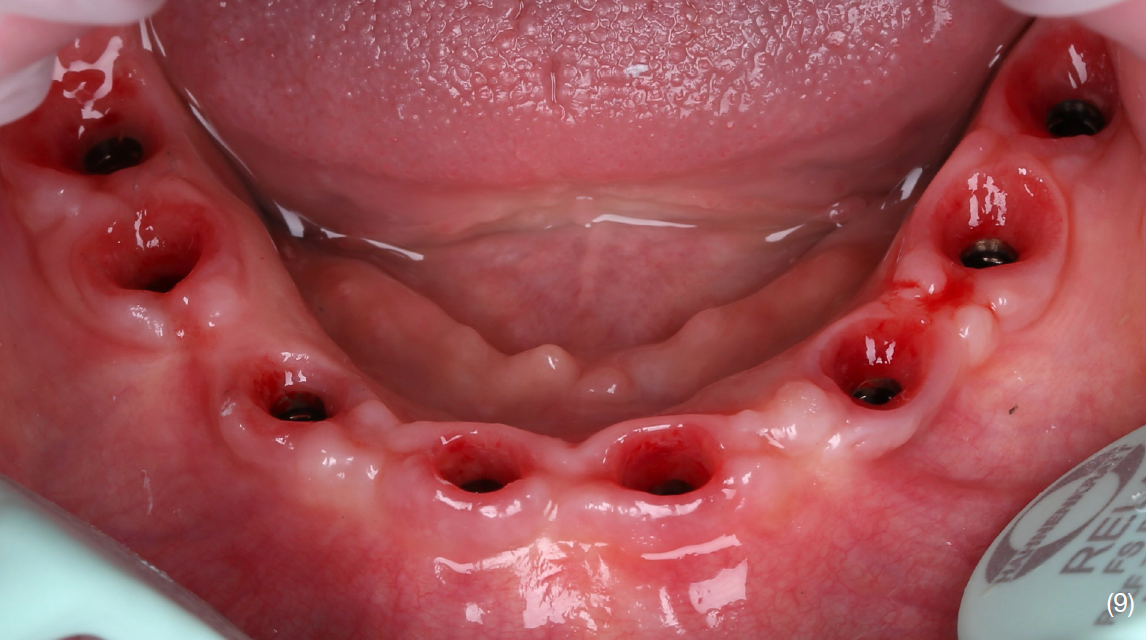

Екстракція наявних зубів та одномоментне встановлення 8 імплантатів Straumann BLT з використанням навігаційного хірургічного шаблону. В це ж відвідування було зафіксовано тимчасову конструкцію з рівня імплантатів, без використання мультиюніт-абатментів. Станом на цей момент для тимчасової реабілітації верхньої щелепи вже було виготовлено та зафіксовано провізорну конструкцію з опорою на зуби.

Через 4 місяці після імплантації на нижній щелепі пацієнт був викликаний для заміни провізорної реставрації на постійну. Було відмічено дефіцит кератинізовних прикріплених ясен в 4 квадранті, що могло поставити під ризик стабільність імплантатів та естетичні параметри.

Тому було проведено м'якотканинну аугментацію технікою Strip в даній ділянці.